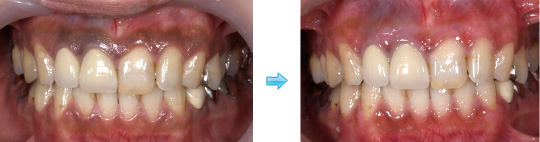

オールセラミック クラウン症例

オールセラミックの最大の利点は光の透過や反射が自然で、現在のクラウンでは最も審美性に優れています。材料学的に生体親和性、科学的安定が高く、着色、変色しないなど、お口の中で経年的に安定した物性を有します。また、物性的にも高強度型セラミック材料の開発により、力学的強度が著しく向上し、臨床的信頼も高まっております。